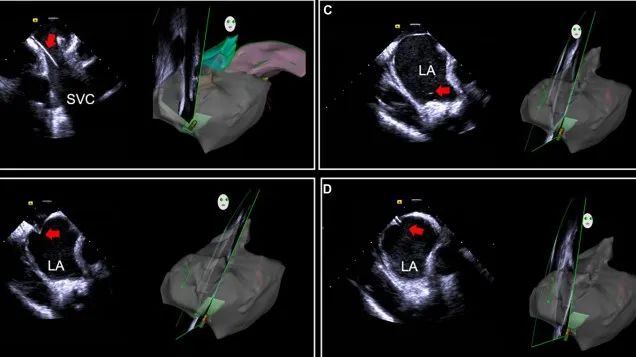

一種與心導管檢查相結合的超聲心動圖診斷新興技術,通過將超聲探頭置于心腔內部,發射并接收超聲信號,來精確獲取心臟解剖結構、心臟血流動力學等信息的實時成像。與其他影像技術相比,ICE技術具有操作簡單、無輻射、安全性高、手術效率高、實用等優勢,ICE在很大程度上有望取代經食道超聲心動圖(TEE),成為電生理和結構性心臟病領域的理想成像方式。

肺動脈高壓手術

心腔內超聲(ICE)技術壁壘極高,國內主要廠商核心部件仍舊為進口,集成了超聲和圖像處理最前端技術,包括超聲探頭、線纜、軟件成像算法等,是當前內窺超聲方向最具挑戰的領域。ICE的應用經歷了2D平面成像、3D三維立體成像、以及4D的實時三維立體成像階段。